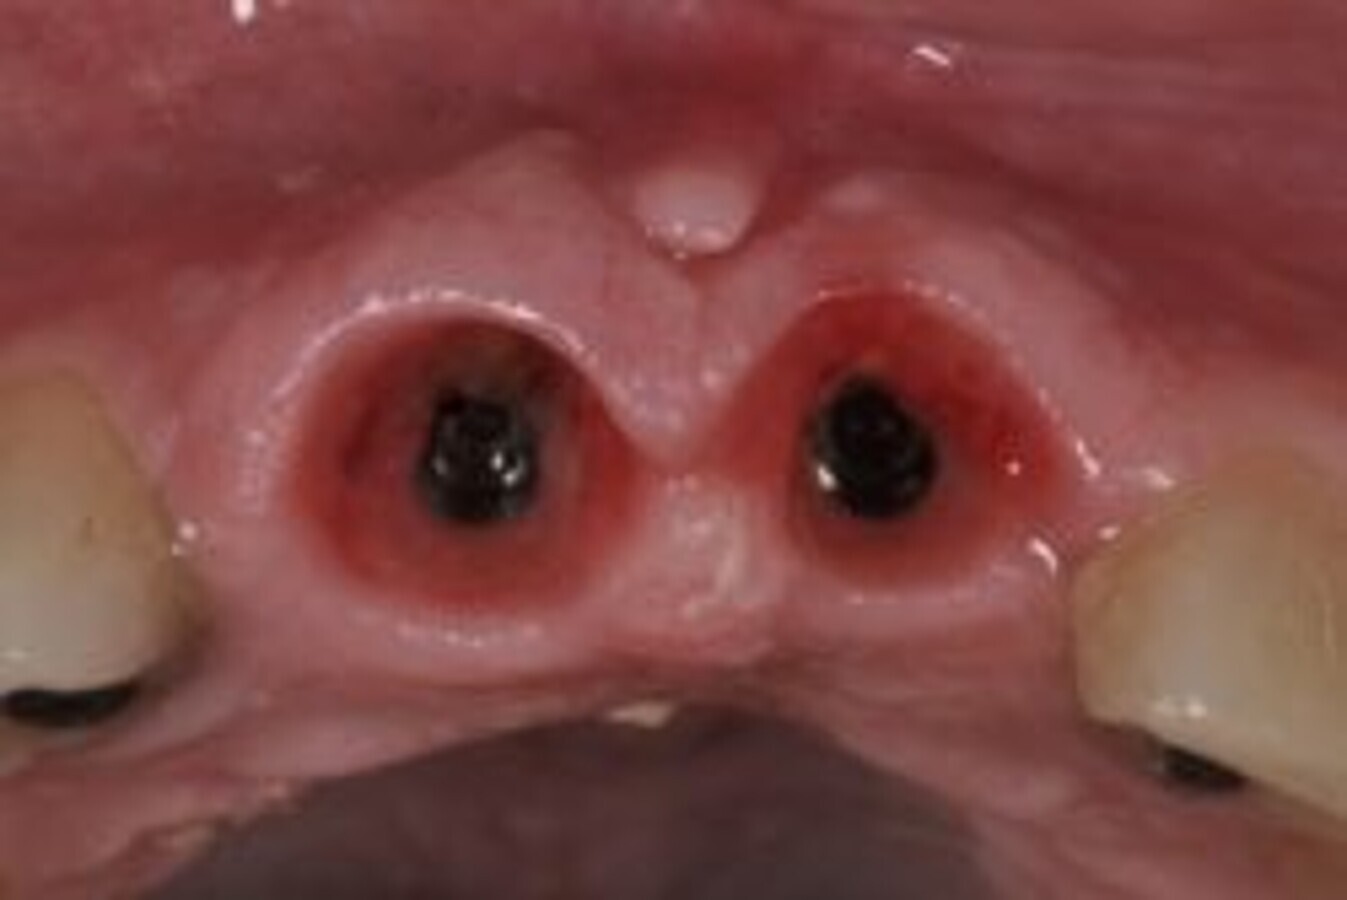

Adjacent socket shields in esthetic zone

The socket shield technique is the only procedure that can prevent the inevitable labial bone loss after extractions of teeth. In my practice, I perform a socket shield procedure for every tooth indicated for an extraction in the esthetic zone, provided the labial plate is intact.

In case the preoperative scan shows an absence of the labial bone, I choose the ‘Early Implant Placement’ strategy as per the ITI guidelines. I see very few indications for the conventional extraction and Dual Zone Grafting protocol in my practice.